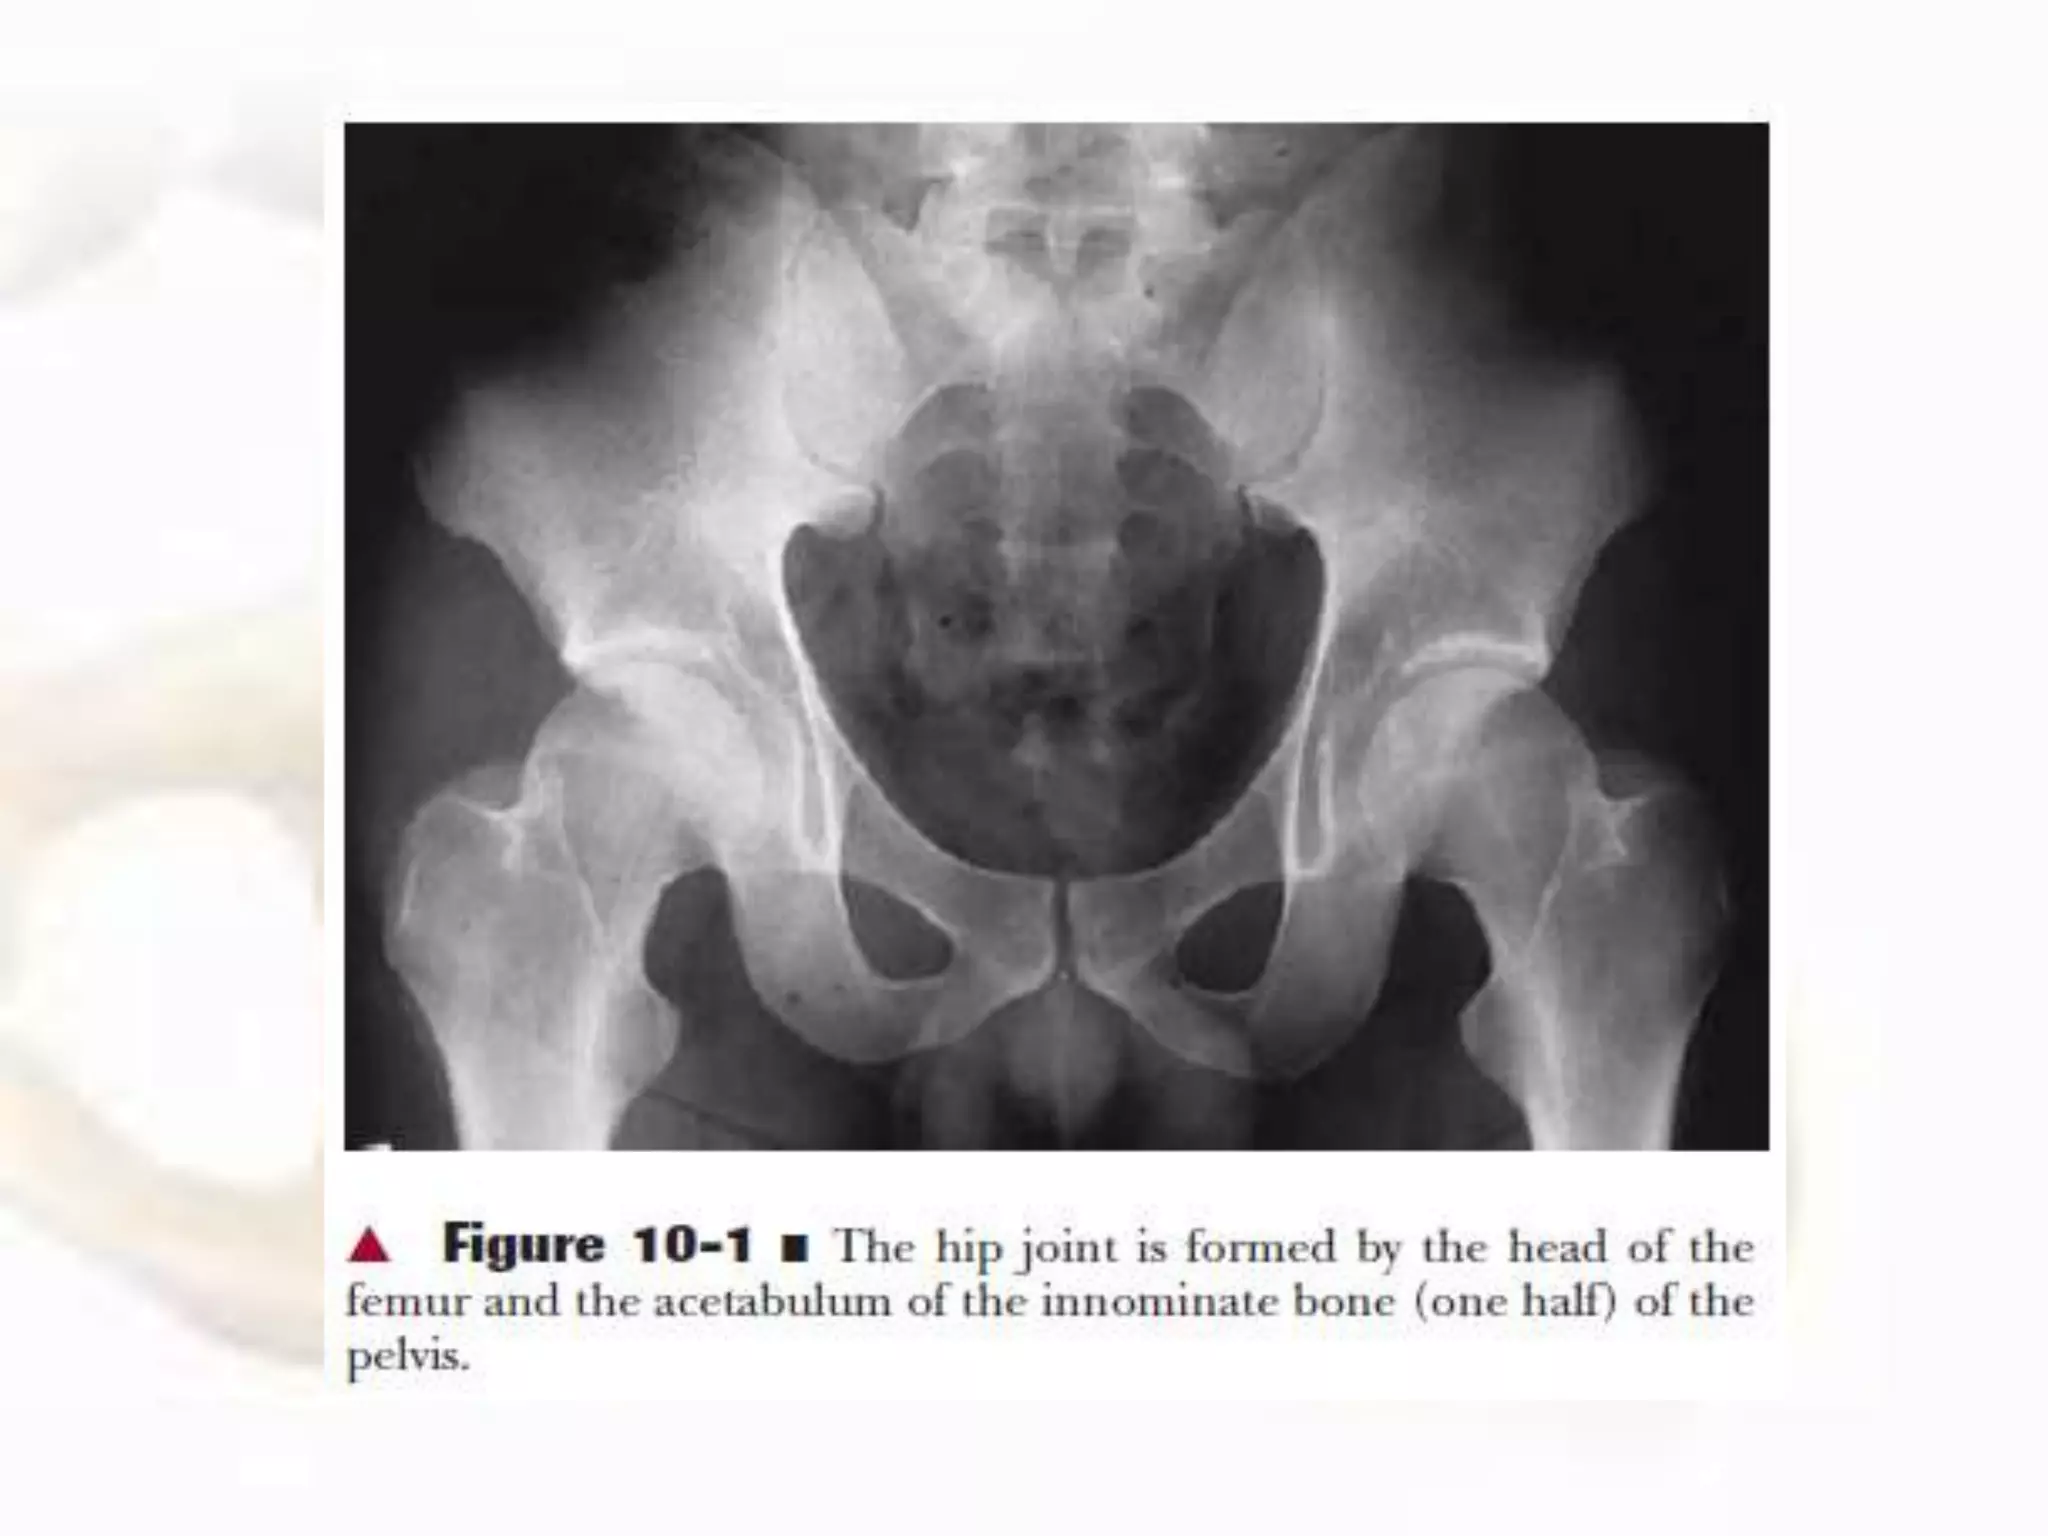

• The hip joint, or coxofemoral joint, is the articulation

of the acetabulum of the pelvis and the head of the

femur.

• The cuplike concave socket of the hip joint is called the

acetabulum and is located on the lateral aspect of the

pelvic bone (innominate or os coxa).